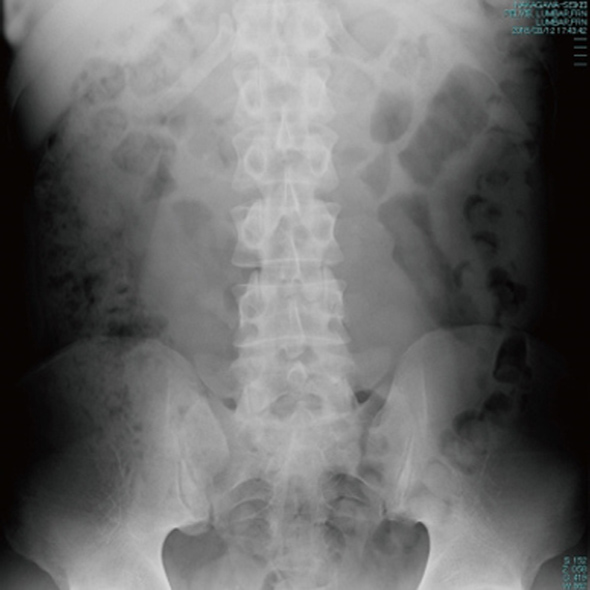

交通事故治療は画像診断が不可欠です。

レントゲンでは、骨折の症状に影響を与えるような経年性変化(加齢変化)を診断します。

エコーは筋や皮下組織の打撲・血腫・神経組織の様子を診断します。

MRIは骨挫傷・神経圧迫・椎間板の突出、靭帯損傷などを診断することができます。